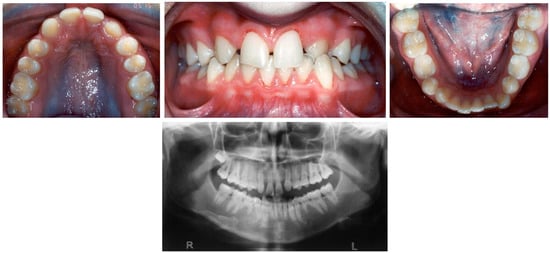

- To demonstrate the clinical management of agenesis of maxillary lateral incisors specifically, because of esthetic concerns, and that of missing second premolars.